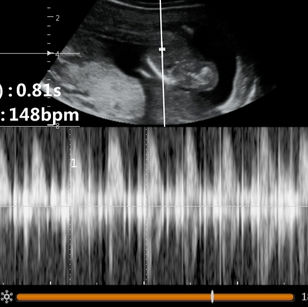

14 Weeks Pregnant

Size: ~3.4 inches (8.7 cm), the size of a Lemon!

Development Highlights:

Body grows faster than head.

Facial muscles can move; baby may make expressions.

Kidneys producing urine.

Baby’s movements more coordinated, though still not felt.